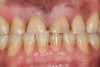

Figure 8  Young adult with signs and symptoms of the bruxism triad: Lateral tooth wear, erosive and abrasive damage to the teeth, and a history of moderate apnea.

Figure 8